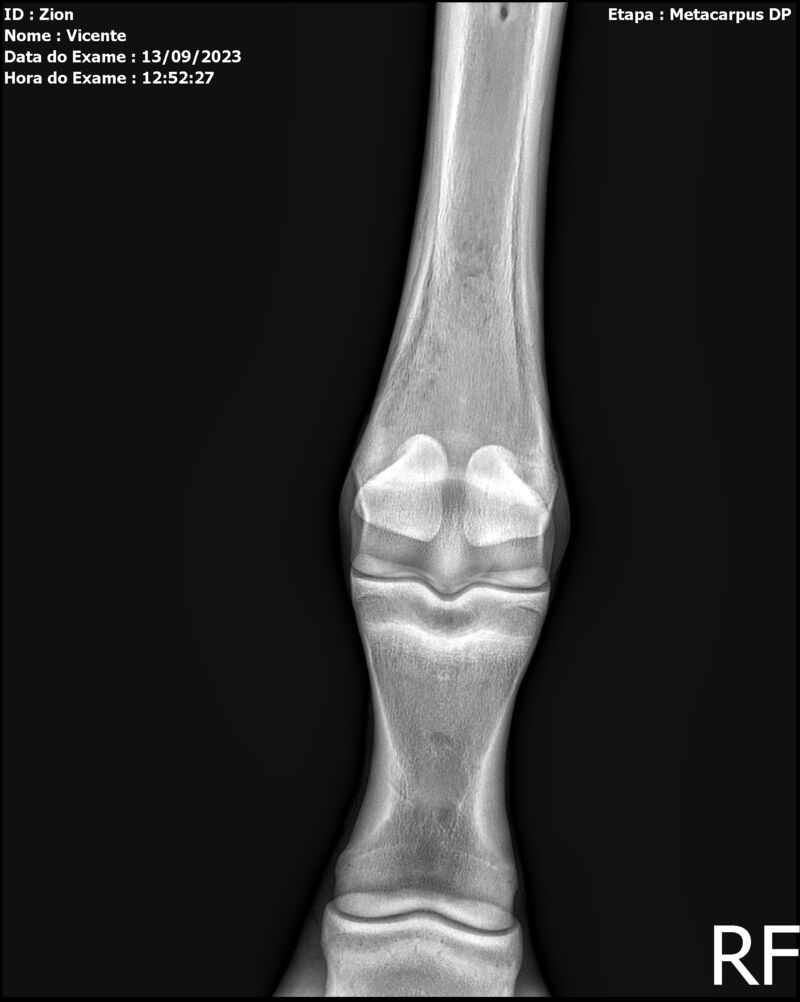

ZION ZC

Raça: BRASILEIRO DE HIPISMO

Sexo: MACHO - POTRO

Nascimento: 17/12/2022

Altura Aproximada: 1,51

Pel.: CASTANHO

Registro: EM AND

Vend.: VICENTE CONTE

Local : PORTO FELIZ/SP